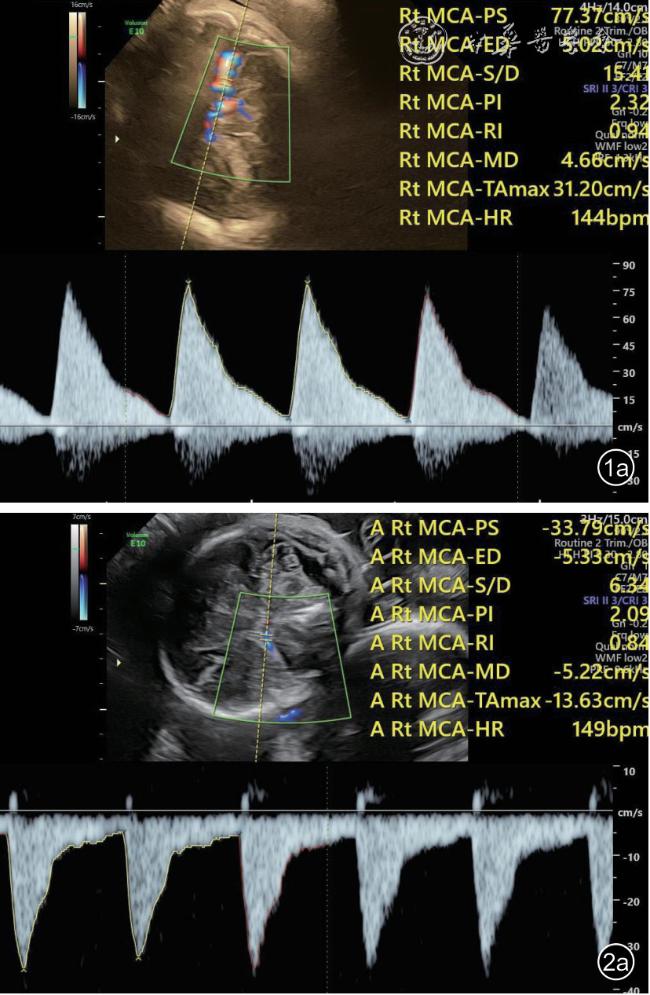

图1 双胎贫血-红细胞增多序列征胎儿孕29+1周产前超声图像。图a:供血儿大脑中动脉峰值流速(MCA-PSV)增高,约1.61 中位数倍数(MoM);图b:受血儿MCA-PSV 降低,约0.87 MoM

26 例TAPS 均在中晚孕期(孕17+1~34+6 周)超声检查中发现,其中Ⅰ期11 例,Ⅱ期3 例,Ⅲ期3 例,Ⅳ期9 例,Ⅴ期0 例。共有的超声特征为:(1)供血儿MCA-PSV 增高(>1.5 MoM),受血儿MCA-PSV 降低(<1.0 MoM)( 图1);(2)“黑白”胎盘:供血儿脐带入口附近胎盘回声增强、增厚,受血儿脐带入口附近胎盘回声减低、较供血儿侧薄(图2)。其他超声特征包括:(1)24例(92%)受血儿肝呈“星空征”(图3);(2)4例(15%)供血儿肠管回声增强(图4);(3)22例(85%)心脏异常,包括心胸比增大、房室瓣反流、房室瓣频谱呈单峰、心肌增厚等征象(图5a、5b);(4)18 例(69%)多普勒血流异常,包括脐动脉、脐静脉、静脉导管A 波异常等;(5)9 例(34%)胎儿水肿,包括皮肤水肿、胸腹腔积液、心包积液;(6)15 例(57%)羊水量不均衡;(7)19 例(73%)脐带异常,包括脐带水肿、脐带插入点异常(图6);(8)15 例(57%)合并双胎选择性宫内生长受限(selective intrauterine growth restriction,sIUGR)、TTTS(表1)。对供血儿及受血儿其他超声特征进行统计分析发现,受血儿肝“星空征”、脐带水肿,供血儿肠道回声增强、胎儿水肿、心胸比增大特征比较,差异有统计学意义(P<0.05,表2)。